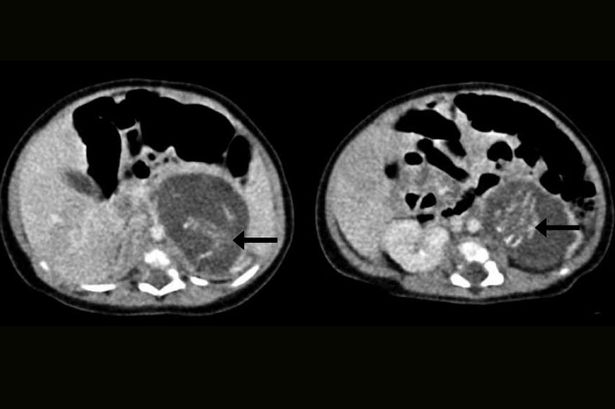

Случаи эмбриона в эмбрионе происходят в среднем один раз на полмиллиона беременностей. О причинах этого явления врачи и ученые спорят. Всемирная организация здравоохранения считает плод внутри новорожденного младенца тератомой (вид опухоли), но гонконгские врачи утверждают, что у их пациентки в организме нашлись два плода близнецов, изначально здоровых, но в ходе беременности поглощенных телом их сестры.

Новорожденную девочку поместили под особое наблюдение гинекологов – врачи подозревали у нее опухоль. Ультразвуковое обследование еще перед родами указало на странное утолщение в брюшной полости.

В итоге трехнедельной девочке сделали операцию: между печенью и почкой хирурги обнаружили два плода. Один из них весил 9,3 грамма, другой — 14,2 грамма, что соответствует примерно восьмой и десятой неделе беременности. У обоих младенцев нашли пуповину, соединенную с плацентоподобной массой в животе девочки.